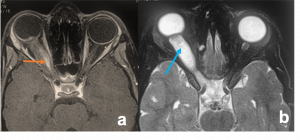

Middle age, Female | Painless, progressive proptosis well-defined (pathologically encapsulated), oval to round | USG- well circumscribed lesion, medium to high internal reflectivity and absent internal flow.

MRI- hypointense relative to muscle on T1, hyperintense on T2. |

Cavernous Malformation. a) Axial T1WI MRI shows a left intraconal ovoid, well encapsulated soft tissue mass that indents the posterior aspect of the eye globe associated with mild proptosis. b)Post contrast axial T1WI with fat suppression demonstrates progressive heterogeneous bright enhancement (white arrow) of the lesion c) USG orbit (B/A) showing a well encapsulated mass on B scan (orange circle) with corresponding internal acoustic reflections on A scan showing characteristic dancing spikes demonstrating rise and fall of waves as it traverses through multiple blood-filled channels within the tumor (blue arrows) |